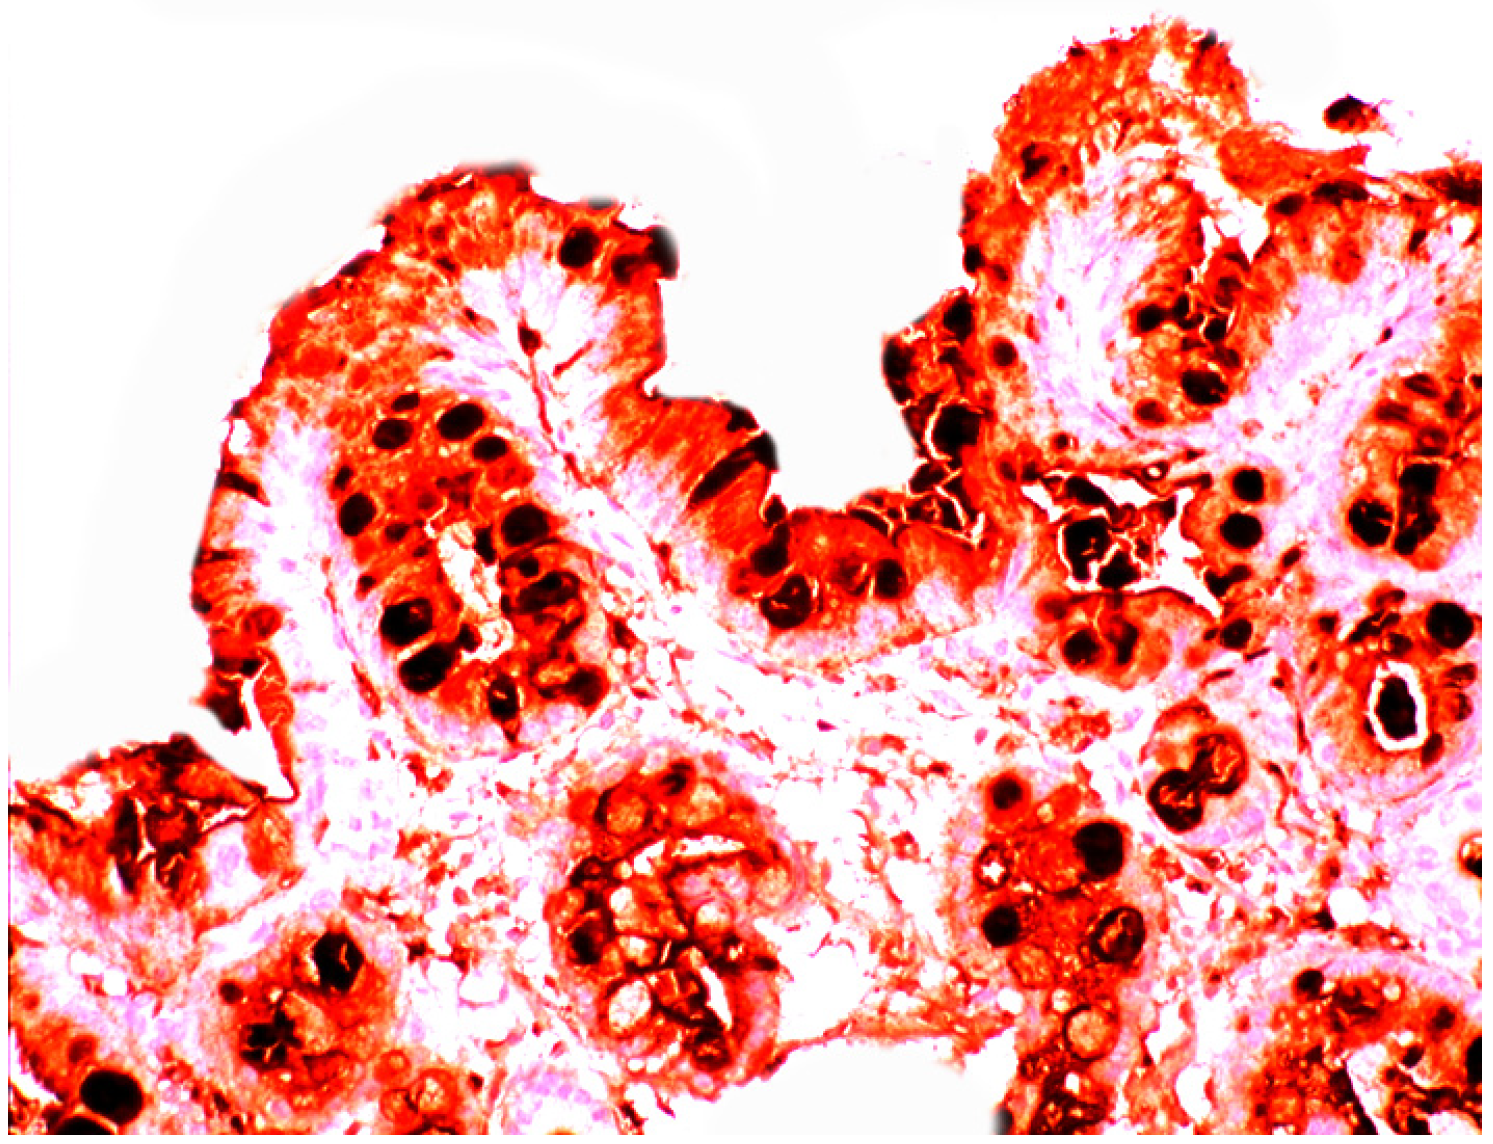

When compared to controls, lysozyme was up-regulated in all three Barrett’s mucosal phenotypes [24]. In some goblet cells, lysozyme was slightly expressed. This phenomenon might be due to a prior goblet cells-discharge of lysozyme-rich intracellular mucus into the lumen (Figure 3). Lysozyme was not expressed in parietal (oxyntic) cells, neither in Barrett’s oesophagus (Figure 4), nor in controls [24].

Close-up view of Barrett’s mucosa of intestinal phenotype, showing faintly stained goblet cells and at arrow, marked lysozyme expression in the secreted mucus, in the lumen of the gland (lysozyme immunostain, ×40).